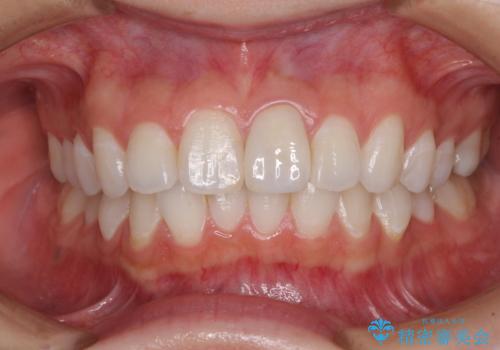

出っ歯に仕上がってしまった前歯 セラミッククラウンの作り替え

- 以前治療した時から、前歯のセラミックが張り出しているのが気になるとのことで来院された患者様です。

作り替えるべきが悩みましたが、どうしても気になるとのことで、処置を行うこととしました。

前歯1歯でのオールセラミッククラウンでは、オーダーメイドタイプのクラウンを選択していただき、周辺の歯と色調を合わせるようにするのですが、今回は既製タイプを選択されました。